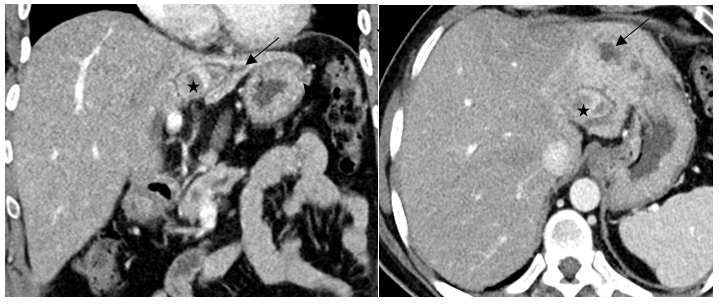

Mapping of the esophago-gastric junction (EGJ)

On some radiographs in adult patients with GERD during the contraction of the LES, it is noticeably shorter than normal both due to the opening of its proximal and distal (abdominal) parts. In such cases contracted only the segment of the LES that is in the diaphragmic (hiatal) channel. On numerous radiographs, the minimum length of this segment was 1 cm. By comparing different radiographs and determining the true dimensions, I was able to determine the different parts of the LES and their relationship with the CD, i.e., create a map of the EGJ. A typical example is shown in Figure 2 a. b. c.

Figure 2. Radiograph (A) and scheme to it (B) of patient with GERD was done in a horizontal position with the abdominal compression. The sharp shortening of the LES because of the opening of the supra-diaphragmatic part of the LES (yellow) and inside the abdominal part of the LES (red) is determined. Only the diaphragm part (blue) of the sphincter is closed. (C). Radiograph of this patient in an upright position taken during abdominal compression. The LES contracted in response to the increased pressure in the stomach. It is visible as two longitudinal folds between the esophagus and stomach. Since the actual height of D-10 is ≈2 cm, the actual length of the LES is ≈3.4 cm. The LES parts: red - the abdominal segment, blue - inside the diaphragm, yellow - above the diaphragm. (D). Three-dimensional model of the EGJ from the article by Yassi et al [48]. The length of the LES is 3.4 cm (blue). Its abdominal part is ≈2 cm. About 1 cm is located at the level of the CD and 0.4 cm above the diaphragm.